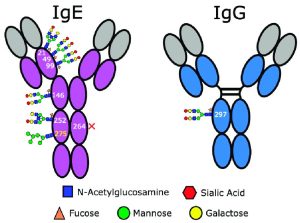

Recent advances in computational and machine learning sciences have had a substantial impact on the antibody discovery process. Novel protocols that incorporate computational approaches can now be used to generate functional antibody therapeutics with good developability. In silico methods complement existing experimental strategies, and their use has become more mainstream in the biopharmaceutical industry. However, the application of computational de novo design strategies requires a thorough understanding of their capabilities, limitations, and experimental validation, as well as their place in the overall discovery pipeline and value chain.